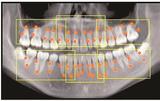

自宅や路上など病院外で亡くなり、死因不明として警察が関与する異状死体(変死体)。山陰両県でも年間1800体以上が発見される今、鳥取大医学部の法医学分野で遺体を解剖する前にコンピューター断層撮影(CT)の画像を活用して死因を究明する「死亡時画像診断(Ai=エーアイ)」が進む。遺体にメスを入れず、画像から情報を読み解く手法は、高齢化の進展で到来した多死社会に何をもたらすのか。Aiの現場を追った。

Ai 解剖=Autopsy(オートプシー)、画像技術=imaging(イメージング)の略